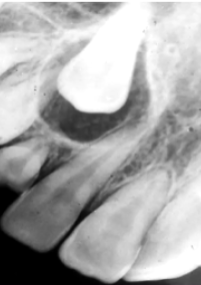

Describe 4 Features of Ameloblastoma?

1) Often Asymptomatic

2) Bucco-Lingual Expansion - degree of facial swelling

3) Root Resorption or Displacement

4) Commonly Multi-locular but can be Uni-locular on Radiographs

How can you differentiate an Odontogenic Keratocyst from an Ameloblastoma?

Amelobastoma have Bucco-Lingual Expansion, whereas an Odontogenic Keratocyst have antero-posterior expansion